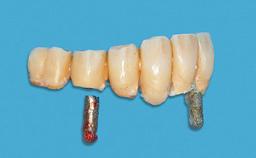

Four Immediately Loaded Mini-Implants Supporting a Mandibular Overdenture

# of Implants 4

Type of Implants One-Piece|Reduced-Diameter

Prosthesis Type RDP

Defining Characteristics Fully edentulous lower jaw to be rehabilitated with an implant-borne removable overdenture